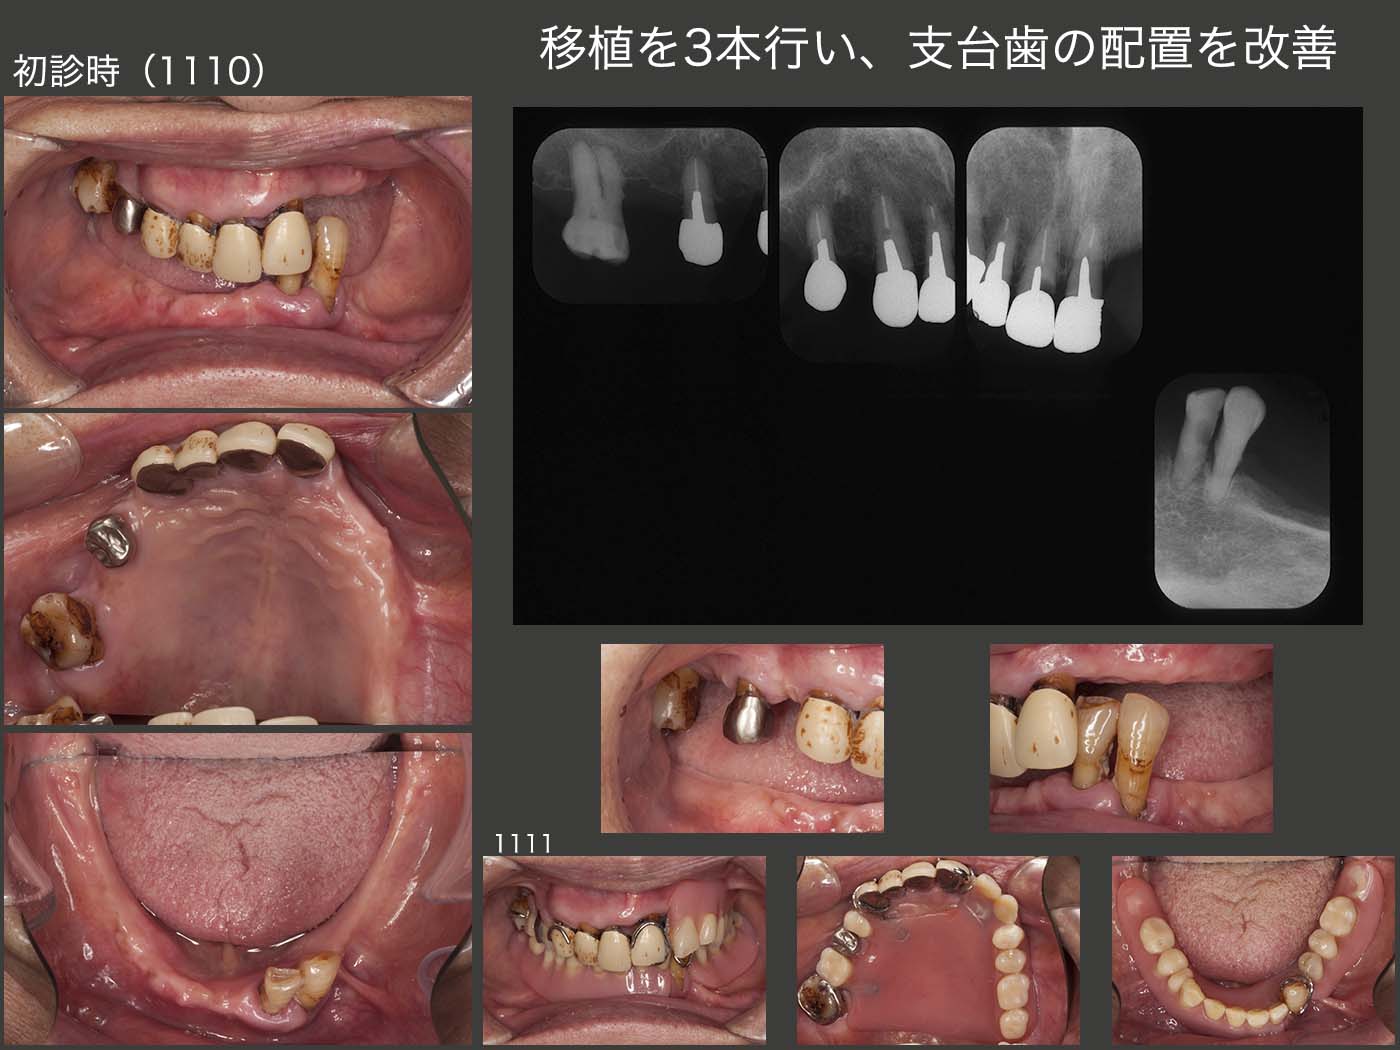

8.移植を3本行い、支台歯の配置を改善

2011年10月初診,76歳女性.10年位前から義歯を使用しておらず,唯一上下咬合している前歯で細々と食事していたが,痛みが生じ,限界に達したため来院.まず,義歯に対する反応をみるために,11月に暫間義歯を装着した.義歯を装着して食事は何とかとれるようになったが,義歯の大きさによる異物感,発音障害等が気になるとのこと.通常,片顎の四隅に歯があれば,義歯を安定させることができる.一歩譲って左右側に歯があれば,何とか義歯を安定させることができる.しかし片側だけでは,いくら歯の数が多くても,反対側の義歯の安定を得ることは難しい.

そこでまず,対合歯のない右上1,2に矯正的挺出力を加え,抜歯しやすいように細工したのちに,2012年2月に右下の顎堤に移植した.なお,矯正用のミニインプラントを植立し,移植歯の暫間固定を図った.

12年3月,今度は右上5に矯正的挺出力を加えたのち,4月に左上の顎堤に移植した.なお,受容側である左上の顎堤が狭かったので,顎堤を少し拡大した.さらに,移植歯と左上1とを暫間固定した.

初診時および初診終了時のパノラマX線写真の比較.歯の垂直・水平的配置は,初診終了後のほうが遥かに良い.ここで,インプラントを用いるほうがよいという意見もあると思う.それも一理であるし,否定もしない.しかし,移植でも対応可能であれば,移植の方が好ましいと考えている.

初診終了後の経過を示す.まず,2015年12月,右下4の移植歯が自然脱落してしまった.この歯は,初診終了時から歯の動揺がみられた.移植の手技が稚拙であったと言わざるを得ない.

つぎに,17年10月,左上1の内冠が歯冠破折し,コアごと脱離した.歯肉縁上歯質がないため,軸面のある内冠を再製作するのは難しい.そこで,支台歯に加わる側方力を少しでも少なくするために,根面アタッチメント(OPA)を装着した.なお,外冠をこのまま再利用できるというのも大きな利点であると同時に,根面アタッチメント周囲を開放できるのも大変好ましい.

18年12月,今度は左上3(移植歯)の動揺が著しくなり,抜歯となってしまった.左上3の歯周ポケットは,移植後は3mm以下で,この状態が12年から15年まで続いた.15年7月に最大5mmになり,18年12月に最大7mmに達した.支台歯の清掃は十分に行われていることから,抜歯の原因は,咬合力に耐えられなかったからと推測される.

20年7月現在,口腔内はとりあえず安定している.それにしても,移植した3本中,2本が抜歯となってしまったことについては,力に負けてしまったことが一番の要因と思われる.また,如何せん移植歯の歯根が短いことも影響しているように思われる.もっと歯根を深く埋入させるべきであったと反省する次第である.